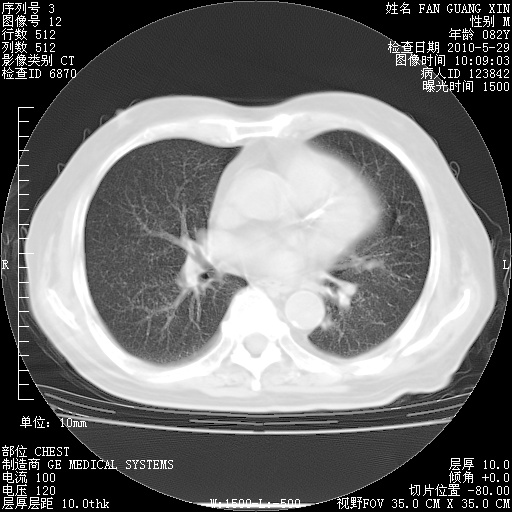

再治疗10天后的肺部CT 纵膈窗

阅读此次胸部CT,肺间质渗出性改变较入院时有吸收。目前从体温、白细胞、中性分叶明显增高,肯定存在细菌感染(发生医院感染哦,若无消化道及泌尿系统等感染的依据,肺部感染可能大)。若你院头孢哌酮舒巴坦钠耐药率较高,同意你的方案,若48小时体温仍高,可考虑使用碳青霉稀类抗菌药物,同时可予超声雾化、注意滴数时加大液体量。白蛋白33.30g/L较低哦,需加强营养等支持治疗。